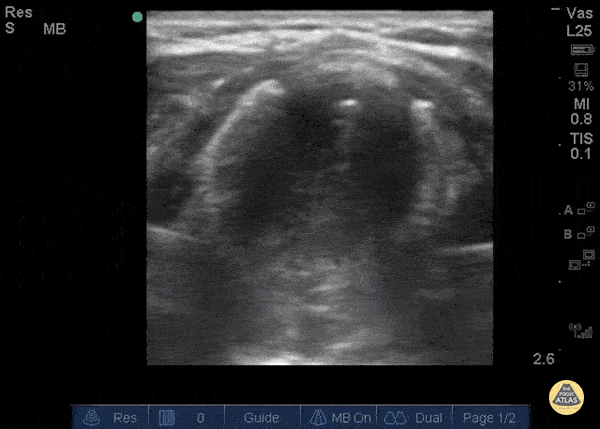

Pediatrics - Tracheal Stenosis

The patient, presenting with stridor, is supine and the airway is seen from the anterior neck in transverse orientation. As the probe is fanned, the bright white line is seen to widen. This column of air moves with inspiration. At its narrowest it is only a few millimeters wide. Growth along the lateral tracheal walls has caused significant tracheal stenosis. In this case, US was used to determine the width of the tracheal column and determine that passage of an ETT would not be feasible. The patient was taken to the OR for an emergent surgical airway. Use of US to estimate tracheal diameter is a novel application. Andrew Liteplo MD, RDMS - Massachusetts General Hospital Chief, Division of Ultrasound in Emergency Medicine Director, Emergency Ultrasound Fellowship